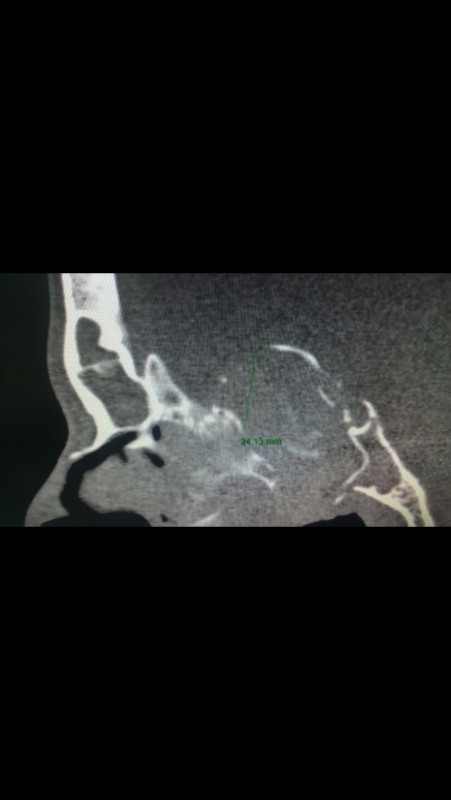

نجح فريق طبي بمستشفى عسير المركزي في إجراء عملية معقدة بواسطة المنظار الجراحي لمريض كان يعاني من التهاب فطري تحسسي في الجيوب الأنفية، مما أدى إلى تآكل قاع الجمجمة وامتد إلى داخل الدماغ بما يقارب ٢ سم، وتم استئصاله بالمنظار، مع العلم أن مثل هذه الحالات المرضية كانت تستدعي التدخل جراحياً بفتح الجمجمة عن طريق أطباء المخ والأعصاب، وقد تكللت العملية بالنجاح وغادر المريض المستشفى وهو يتمتع بالصحة والعافية.

من جهته قال رئيس الفريق الطبي الذي أجرى العملية الدكتور علي حسن الزرعي استشاري أمراض الأنف والجيوب الأنفية وجراحة قاع الجمجمة بأن التهاب الجيوب الأنفية الفطري التحسسي تبدأ أعراضه بانسداد بالأنف وإفرازات أنفيه، وأحياناً يكون هناك جحوظ وزغللة بالعين وازدواجية في النظر أو فقدان النظر في بعض الأحيان، وقد يصيب هذا المرض جميع الأعمار ويكون امتداده خارج الجيوب الأنفية إلي الدماغ أو العين في الأطفال أكثر منه في الكبار.

وأضاف أنه يتم تشخيص هذا المرض عن طريق المنظار الأنفي والأشعة المقطعية بالإضافة إلى التحليل المجهري، وأشار إلى أنه شارك في إجراء العملية الدكتور إبراهيم صميلي والدكتور ماجد عسيري أخصائي الأنف والأذن والحنجرة وفريق التمريض صالحه عسيري و ابتسام عسيري وطبيب التخدير الدكتور محمد داغستاني .